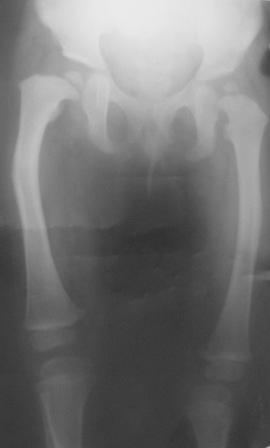

Уважаемые коллеги. Осмотрена девочка 2007г.р. При рождении

двухсторонная косолапость, двухсторонный врожденный вывых бедер,

лечилась консервативно.

В данное время ходит самостоятельно, прихрамывает на прав.ногу, прав.

нога укорочена на 3,5см и и находится в положении внутренней ротации

Планируется подвертельная деротационно-вальгизирующая остеотомия

бедра. или остетомия на верщине деформации бедра с удлиненим по

методу Илизарова.